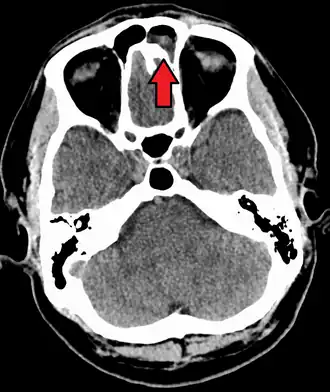

For sinusitis lasting more than 12 weeks, a CT scan is recommended.[66] On a CT scan, acute sinus secretions have a radiodensity of 10 to 25 Hounsfield units (HU). In a more chronic state, they become more viscous, with a radiodensity of 30 to 60 HU.[69]

CT of chronic sinusitis -

CT scan of chronic sinusitis, showing a filled right maxillary sinus with sclerotic thickened bone -